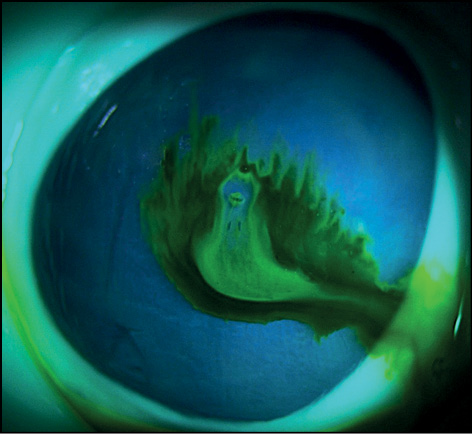

Явление флуоресценции наблюдалось сразу после нанесения красителя на глазную поверхность кадаверных глаз с ОТГ. Флуоресцеин растворялся в вытекающей внутриглазной жидкости и фиксировался по краям раны. Далее отмечалось изменение в окраске потока вытекающей внутриглазной жидкости. Время эксперимента составило 5 секунд (с). В этом временном интервале наблюдали две фазы окрашивания потока вытекающей жидкости. Так, до 2,95 с наблюдали ярко-зелёный поток жидкости (рис. 1, 2). После 2,95 с происходило размывание красителя и разделение основной струи жидкости на несколько потоков с разной степенью интенсивности окрашивания (рис. 3). Через 4,12 с наблюдали уже прозрачный поток вытекающей жидкости в центре и окрашенные зелёные потоки по краям (рис. 4).

Рис. 3. Фаза «прозрачного потока» вытекающей жидкости через 2,95 с после окрашивания флуоресцеином.

Fig. 3. “Clear flow” phase of the escaping fluid 2.95 s after fluorescein staining.

Рис. 4. Фаза «прозрачного потока» вытекающей жидкости через 4,12 с после окрашивания флуоресцеином.

Fig. 4. “Clear flow” phase of the escaping fluid 4.12 s after fluorescein staining.